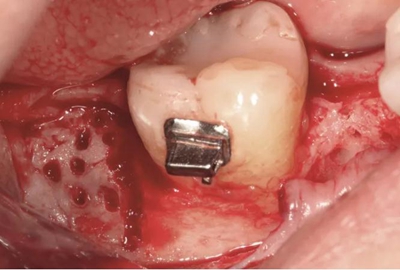

圖5c. 翻全厚瓣后,看到嚴重的牙槽嵴吸收

圖5d. 在骨移植受植處、第二磨牙和第三磨牙牙根之間以及第三磨牙遠中進行去皮質(zhì)術(shù)

圖5e. 去皮質(zhì)后,同種異體凍干骨顆粒放置于受植區(qū)

圖5f. 膠原膜覆蓋并適應于受植區(qū)

手術(shù)切口位于牙槽嵴頂舌側(cè),溝內(nèi)切口向下頜升支的遠中和頰側(cè)延伸,接著翻全厚粘骨膜瓣。牙槽嵴去皮質(zhì)術(shù)在下頜第一磨牙受區(qū)和第二磨牙牙根遠中進行,用一個高速的碳化鎢鋼球鉆和超聲骨刀進行(Piezosurgery, Mectron)(圖2b)。

翻起頰側(cè)瓣后,放置同種異體凍干骨(freeze-dried bone allograft,F(xiàn)DBA),并覆蓋可吸收膠原膜(Osseoguard, Biomet 3i)(圖2c)。第二磨牙遠中去皮質(zhì)區(qū)上放置硫酸鈣(CaSO4, ACESurgical)。瓣主要采用5-0聚四氟乙烯縫線進行水平褥式和牙間間斷縫合,以及連續(xù)縫合(GORE-TEX, W.L.Gore & Associates)。